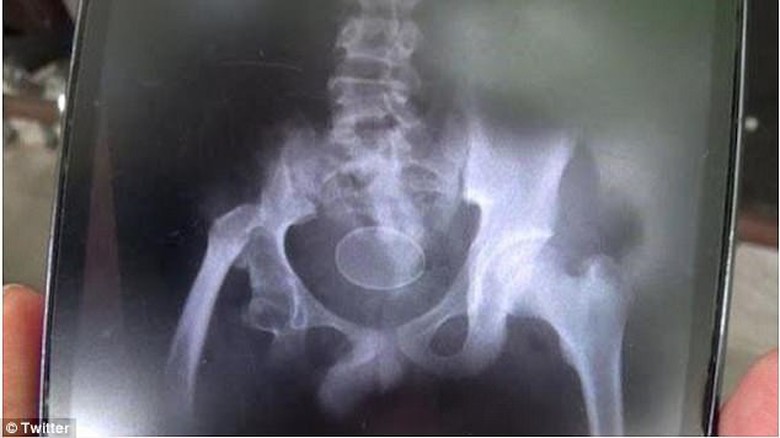

Hình chụp X-Quang cậu bé Akmal. |

Một người phát ngôn từ bệnh viện cho biết: "Tôi nghĩ rằng những quả trứng đó đã được đưa vào người Akmal một cách cố ý. Nhưng chúng tôi cũng không nhìn thấy trực tiếp".

Nghiên cứu mới nhất của các bác sĩ cho thấy những quả trứng lấy ra trong người Akmal đều là trứng gà.